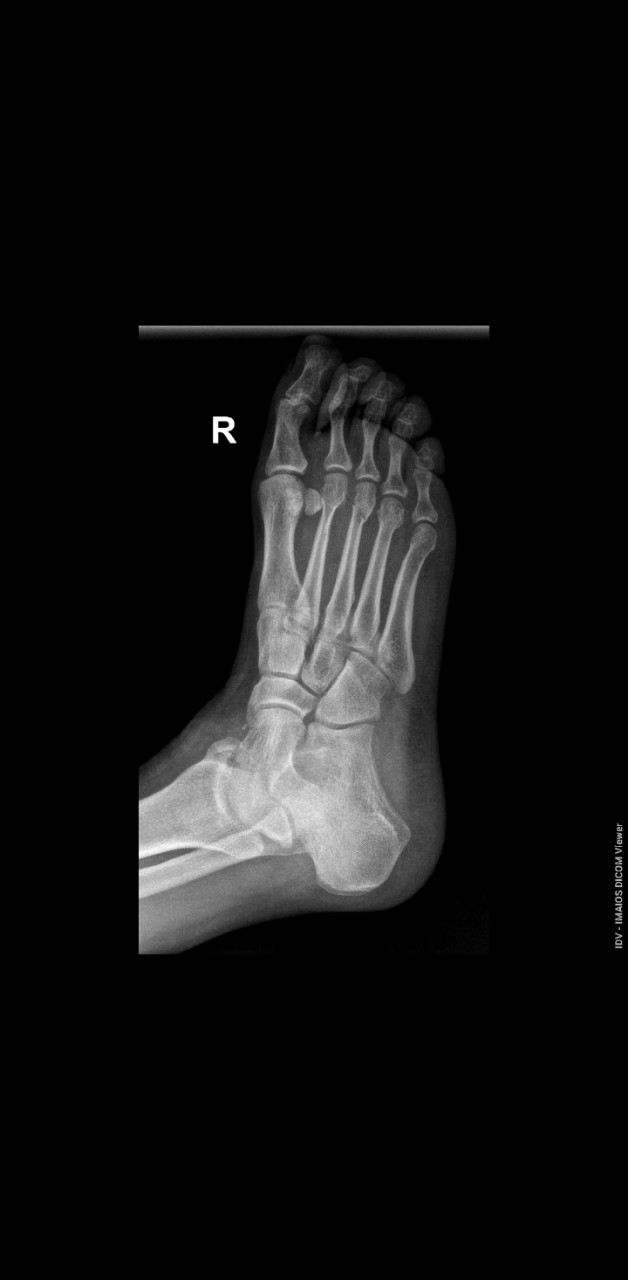

Здравствуйте доктор!  Подскажите, пожалуйста, нужна ли при таком переломе операция или достаточно гипса?

Здравствуйте. На представленных рентгенограммах виден перелом основания пятой плюсневой кости (возможно по типу перелома Джонса). Смещение минимальное, линии перелома ровные. Если нет значительного смещения и фрагменты стабильны тогда обычно достаточно иммобилизации (гипс или ортез) и покоя. Но окончательное решение о тактике лечения принимается очно с учётом симптомов, осмотра и контроля снимков в динамике.